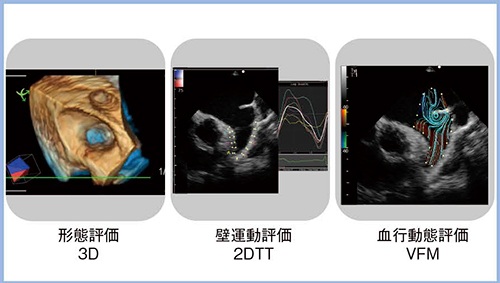

4. 経食道心エコーによる左心耳機能評価

左心耳機能評価に当たっては,経食道心エコー(TEE)による左心耳内血栓のリスク評価が期待されている。図5は,日立製のTEEプローブによる実際の画像であるが,3Dエコーでの形態評価や2DTTによる壁運動評価,“Vector Flow Mapping(VFM)”による血行動態評価が可能で,明瞭に描出されている。

図5 TEEによる左心耳機能評価